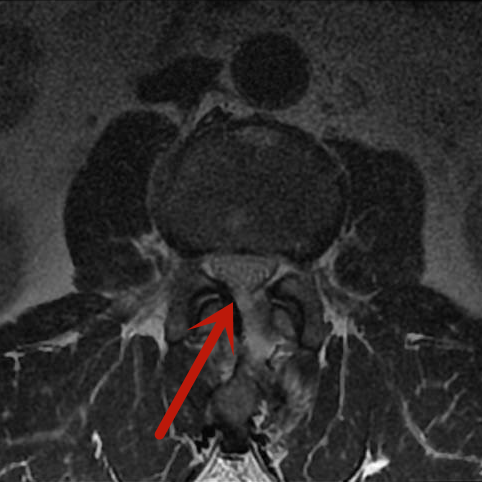

近期,梁先生因双下肢麻木到我院脊柱骨科住院治疗。腰椎磁共振检查显示患者的腰2-3椎管内肿瘤,很大可能性是血管瘤,若不及时手术治疗,随着肿瘤的生长、神经长时间受压,将可能导致双下肢瘫痪、大小便失禁等严重后果。

术前影像

患者肿瘤的大小约3.5cm×1.5cm,别看肿瘤不大,但要在内镜下完全通过0.8cm大小的切口进行肿瘤后方的椎板切除减压、肿瘤与周围神经的分离、肿瘤的暴露、肿瘤的彻底切除,需要娴熟的内镜操作技术。